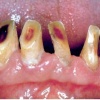

Hamba erosioon

Muu kui katubakterite happe põhjustatud hamba kõvakoe happelist kahjustust nimetatakse erosiooniks. Hape söövitab ehk demineraliseerib hambapinda, muutes selle pehmeks ja nii kiiresti kuluvaks.